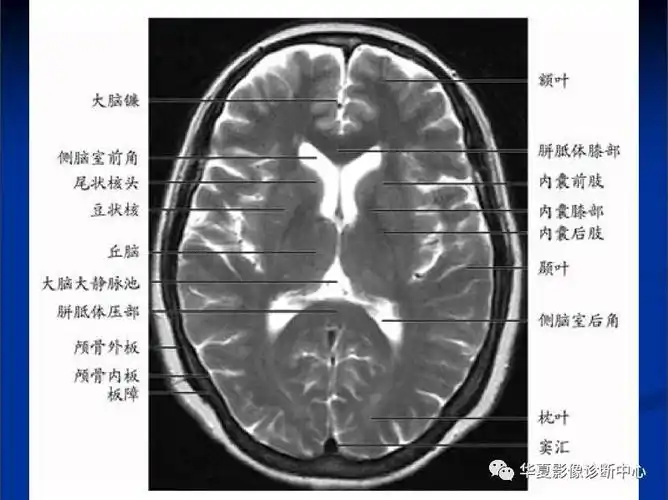

磁共振读片基础初学者看过来